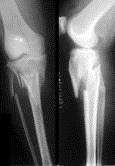

问题 病历摘要: 患者×××,男性,65岁,因车祸致伤左小腿后肿胀、活动受限、疼痛2小时。查体:左小腿上端肿胀,触痛(+),触及在骨擦音,左足伸足母、伸趾功能正常,足背动脉搏动正常。 关于胫骨髁骨折给膝关节功能造成的后果下列叙述哪些是正确的?

选项 A、关节内出血,如再加以外固定,出血与髌上囊粘连,使膝关节伸及屈曲功能发生障碍,不用外固定,早期活动关节可防止或减轻粘连 B、髁骨折劈裂下陷,使胫平台关节不平滑,继而可发生创伤性关节炎 C、伴有侧副韧带或交叉韧带损伤,以及髁下陷后,该侧副韧带亦相对松驰,造成膝关节不稳定 D、单侧髁骨折下陷,致膝关节向该侧倾斜,为外翻或内翻畸形